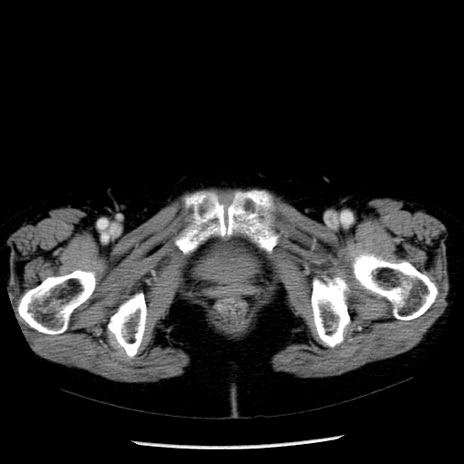

症例13(横断像)

【症例】70歳代女性

【主訴】腹痛、嘔吐

【現病歴】15時間程前(昨晩)より腹痛あり。今朝になっても症状の改善なく、嘔吐あり。腹痛も増悪あり、救急外来受診。

【既往歴】子宮癌全摘術後

【身体所見】意識清明、BP 121/72mmHg、P 74bpm、SpO2 100%(RA)、腹部:平坦・軟、腸雑音ほぼ聴取せず。下腹部・心窩部・臍左上に圧痛あり。反跳痛なし。

【データ】WBC 10600、CRP 0.15